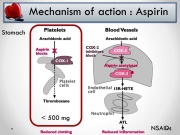

| 08:21, 28 באוקטובר 2017 | Aspirin8.jpg (קובץ) |  |

84 קילו־בייטים | Motyk | 1 | |